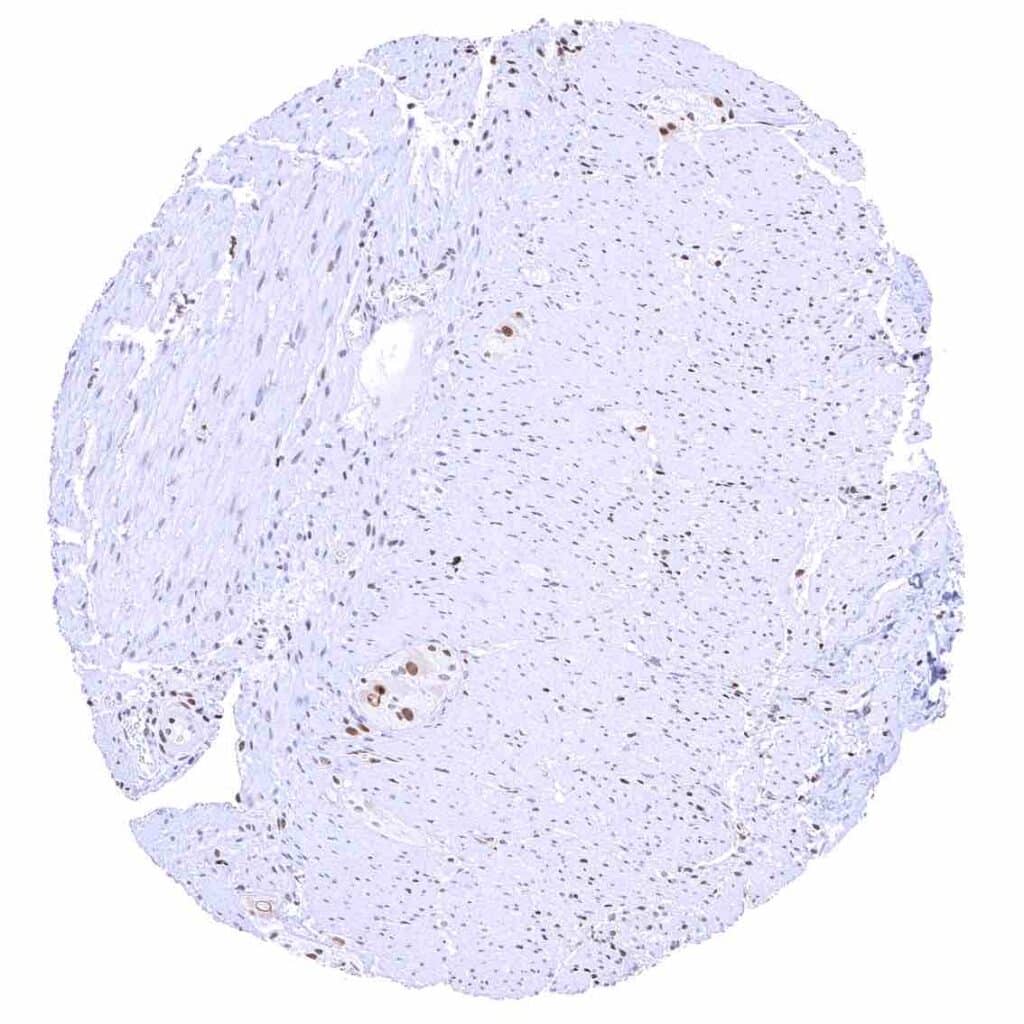

Heart muscle – Distinct nuclear p27 staining of stroma cells while myocytes are largely negative.